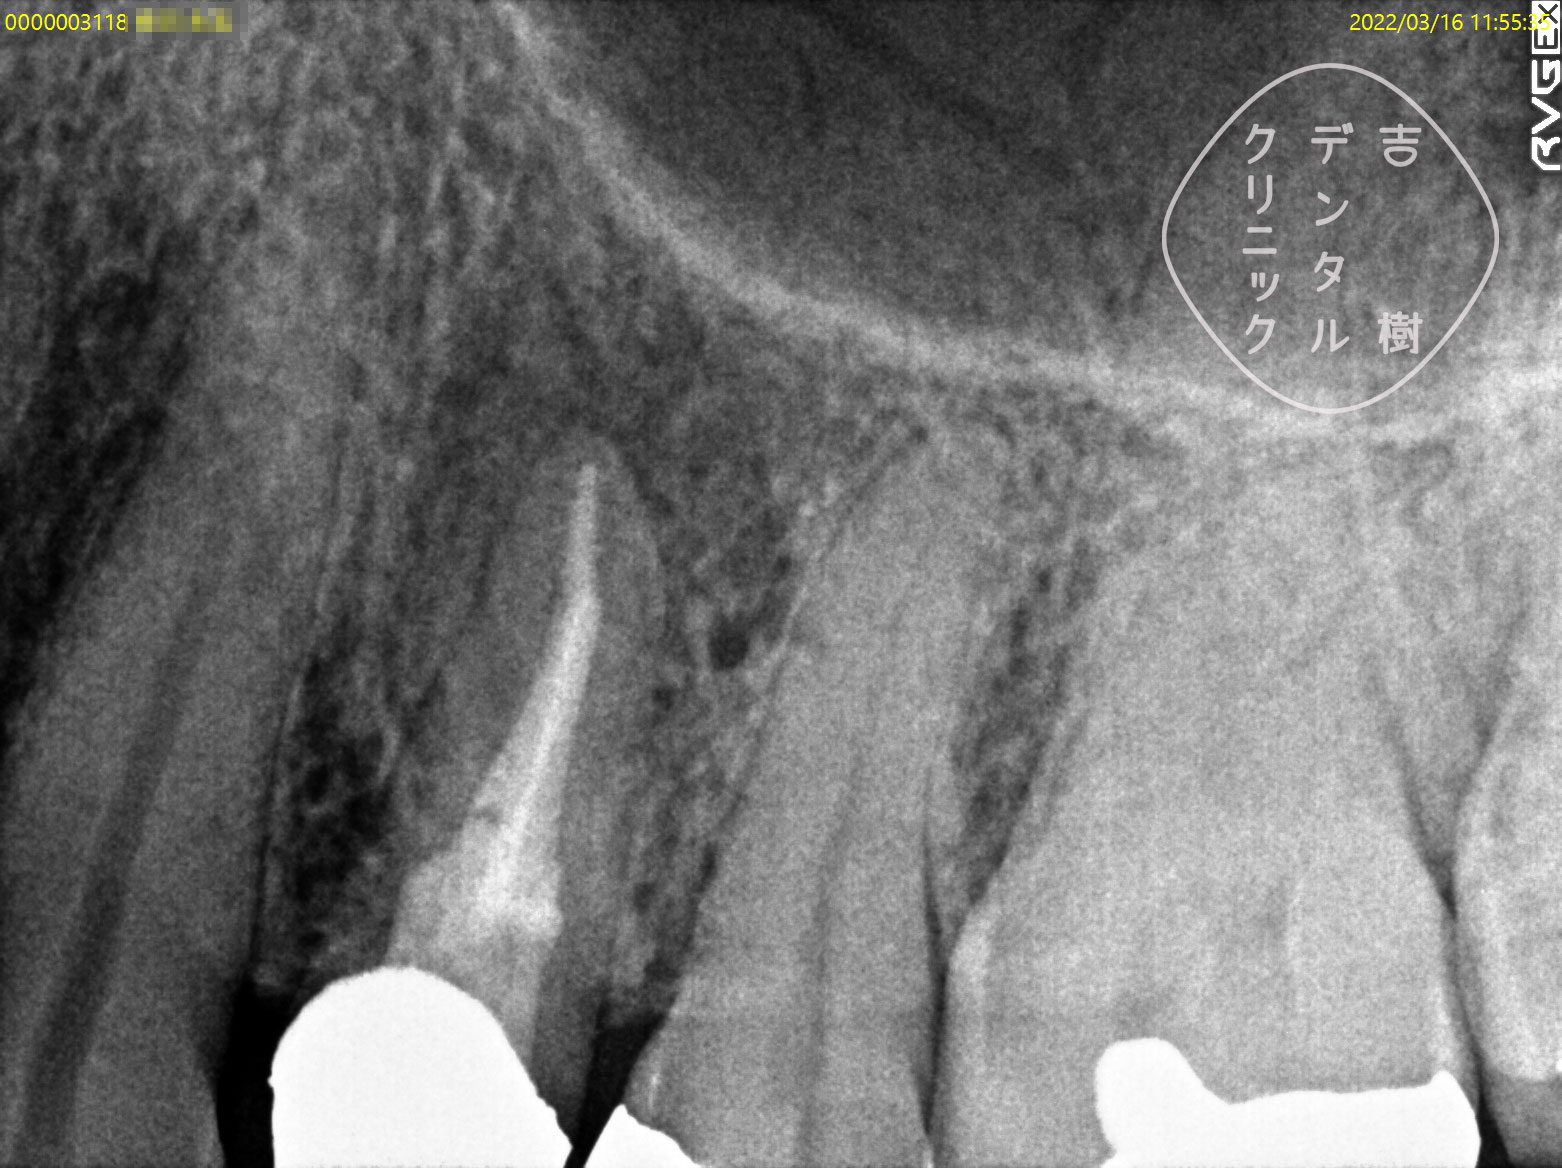

他院で抜歯と診断されたが、当院で根管治療を行い抜歯せずに治療できたケース。

根管治療を行う際には、まず、画像診断を行うことで歯の形状を確認します。通常、多くの歯科医院では「2次元」のレントゲンが使用されますが、この方法では初期の患部を見つけることが難しく、根管の複雑な形状を確実に把握するには不十分です。

そのため、当院では「3次元」の撮影が可能な「CT」を使用しています。CTはお口の周りを360度回転しながら撮影することで、レントゲンでは確認することができなかった細かい部分まで詳細に把握することができます。